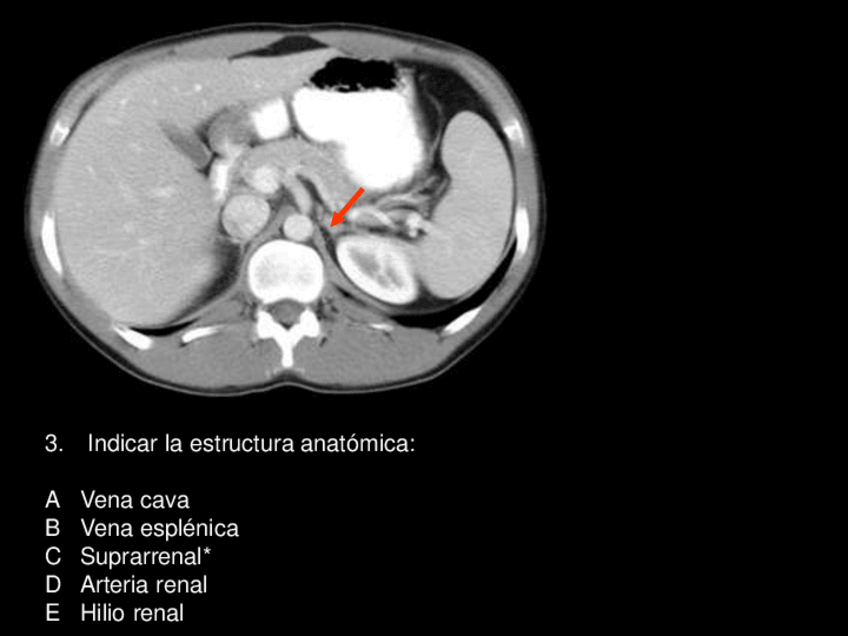

Exámenes - Preguntas-de-rayos-resueltas.pdf

13 páginas